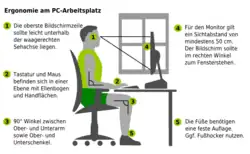

Eine wichtige Maßnahme zur Vorbeugung gegen einen Bandscheibenvorfall ist die richtige Ergonomie am Arbeitsplatz. Das gilt neben den körperlichen Arbeiten auch für Tätigkeiten, die im Sitzen verrichtet werden. Heutzutage gibt es viele ergonomische Lösungen für die Arbeit am Bildschirm, am Schreibtisch und Arbeiten, welche lange statische Sitzpositionen erfordern. Da die Bandscheibe nicht von Blutgefäßen versorgt wird, ist sie auf wechselnde Druckbelastung zum Austausch der Nährflüssigkeit angewiesen, womit statische Sitzpositionen möglichst zu vermeiden sind.[27]